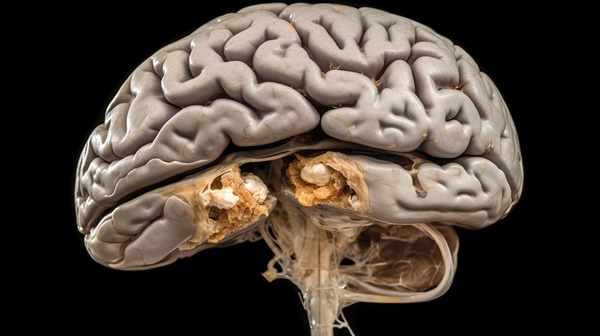

뇌종양이란

뇌종양은 뇌에 생기는 비정상적인 덩어리로, 세포가 제멋대로 자라나며 생깁니다. 흔히 '양성'과 '악성'으로 나뉘는데, 전이를 하지 않는다고 안심할 수만은 없어요. 왜냐하면 뇌라는 공간은 좁고, 중요한 기능이 빼곡히 모여 있기 때문에 아주 작은 종양이라도 큰 영향을 미칠 수 있습니다. 종양이 자라는 위치에 따라 기억력, 말하기, 운동 기능 등에 영향을 줄 수 있지요. 예전에 지인이 아무 증상 없이 정기검진에서 발견됐는데, 알고 보니 뇌에 작은 종양이 자라고 있었더라고요. 증상이 없다고 지나치기보다는, 정기적인 검진이 생각보다 큰 역할을 할 수 있어요